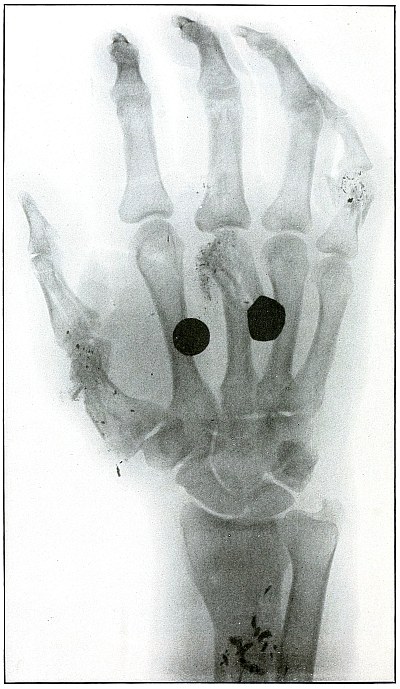

Plate 43.

[Pg 97]

Rifle—Plate 43.

UPPER EXTREMITY.

Gunshot Fracture of the Metacarpus.

Wound of entrance, inner aspect of the hand over proximal end of the

fifth metacarpal.

Wound of exit, on the outer border of the hand over the distal end of

the second metacarpal.

The velocity of the bullet was in mid or long range, as it displaced

no fragments, and as it made a point of entrance and exit about the

same in appearance.

The wound was infected, which is more frequently the case in the hand

than in the forearm.

The treatment is conservative with free incision and drainage

in the management of infection.